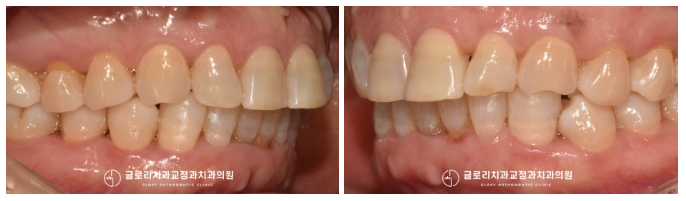

중랑구교정치과 에서는

앞서 계획했던 대로 눈에 띄지 않는

혀쪽 표면에 장치를 부착하여

본격적인 치아 이동을 도왔는데요.

눈에 띄지 않아 심미성은

매우 좋은 편에 속하지만,

『그렇게 8달이 흐르고

모든 과정을 마칠 수 있었습니다!』

안으로 들어가 있던 하악 치아가

올곧게 자리를 잡아 고르게 배열되어 있는데요.

이때 벌어진 틈새를 메꾸기 위해

레진 수복도 함께 도와드렸더니

심미성이 배가 되어 훨씬 건강한 모습으로

바뀐 것을 볼 수 있었습니다.

무엇보다 삐뚤어진 곳이

고르게 펴지게 되어 위생관리가

훨씬 편해지셨다는 말씀을 하셨는데요.